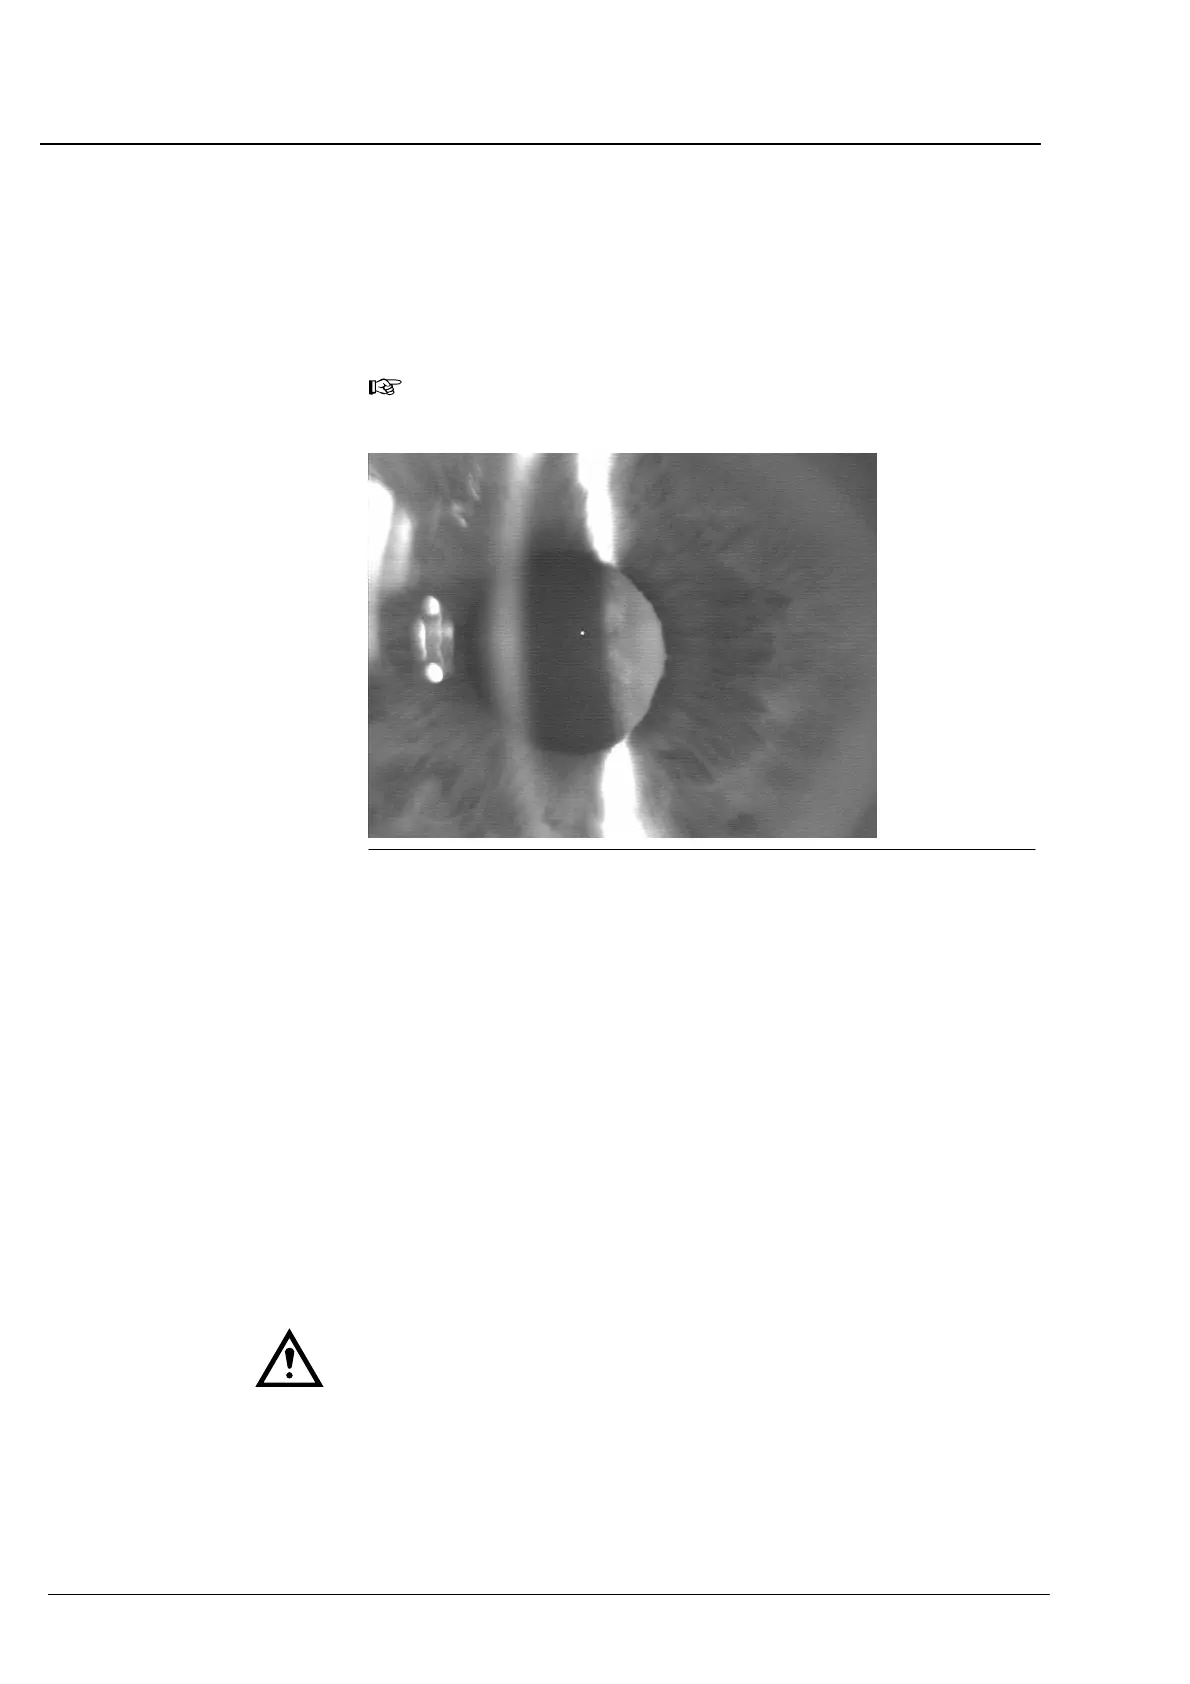

Abb. 63 Optimal eingestellter Lichtschnitt (Linse mit Katarakt)

Die Abb. 62 und Abb. 63 zeigen Lichtschnitte rechter Augen.

Die Gebilde links vom Hornhautbild sind direkte Reflexbilder der leuchĆ

tenden Lichtaustrittsfläche des seitlichen Spaltprojektors. Zur BerechĆ

nung der Vorderkammertiefe sind diese Reflexe nicht notwendig; sie

dürfen das Bild der Hornhaut nicht beeinflussen (siehe unten).

Am linken Bildrand sind außerdem Reflexbilder, der vor dem Patienten

liegenden Umwelt (hier ein Fenster) zu erkennen. Je nach den BeleuchĆ

tungsbedingungen im Untersuchungsraum kann auch das Bild der

Frontseite des IOLMasters, welches die Hornhaut entwirft, zu sehen

sein. Diese Artefakte stören die Vorderkammertiefenmessung nicht,

wenn die wichtigen Bilddetails (HornhautĆ und Linsenbild) sowie das

Fixierpunktbild nicht von solcher Art Nebenlicht überstrahlt werden.